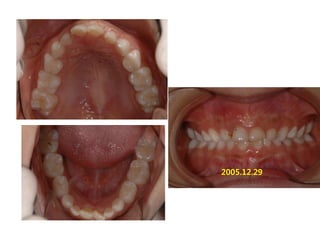

1998.09.25/M

C.C

• Max. protrusion

Dx

• Mentalis action, incorrect tongue posture

Goal

• Establish perioral muscle tone and tongue

posture

2005.12.29

2008.07.01

Start T4K